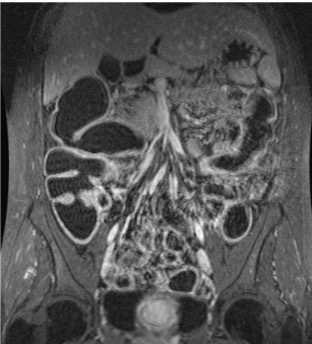

Abdomenal MRI